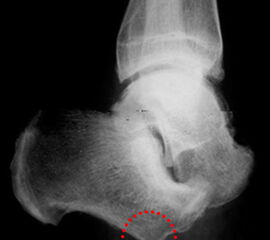

Nekrose an der Großzehe (Abb. 2)

Die Strahlresektion sollte wegen der Gefahr eines Ulkusrezidivs der Exartikulation im MTP Gelenk vorgezogen werden!

• Lokale Osteomyelitiden mit Knochennekrose und Weichteilbeteiligung (Abb. 50).